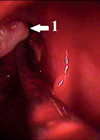

Isshiki Thyroplasty Type 2

Indication Adductor spasmodic dysphonia is a neurological condition of unknown aetiology. The symptoms are believed to be caused by involuntary contraction of the adductor muscles of the vocal cord as a result of an abnormality of neurotransmitters in the basal...